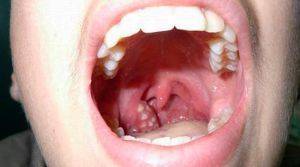

Гнойные образования на гландах и задней стенке гортани всегда указывают на наличие инфекционного процесса у пациента. Наиболее часто воспаление вызывают такие микроорганизмы, как стафилококки, стрептококки, пневмококки и энтерококки. Однако также могут быть виновниками аденовирусы или грибки рода Кандида. В таких случаях на гландах формируются белые комки, а гортань покрывается налетом, напоминающим творог.

Кроме того, гной в горле чаще всего является признаком ангины, которая может привести к серьезным осложнениям, затрагивающим сердце, почки, легкие и другие внутренние органы. Поэтому, если вы заметили подозрительные пятна, белые точки или гнойники на миндалинах, необходимо незамедлительно обратиться к врачу, а в идеале вызвать специалиста на дом.